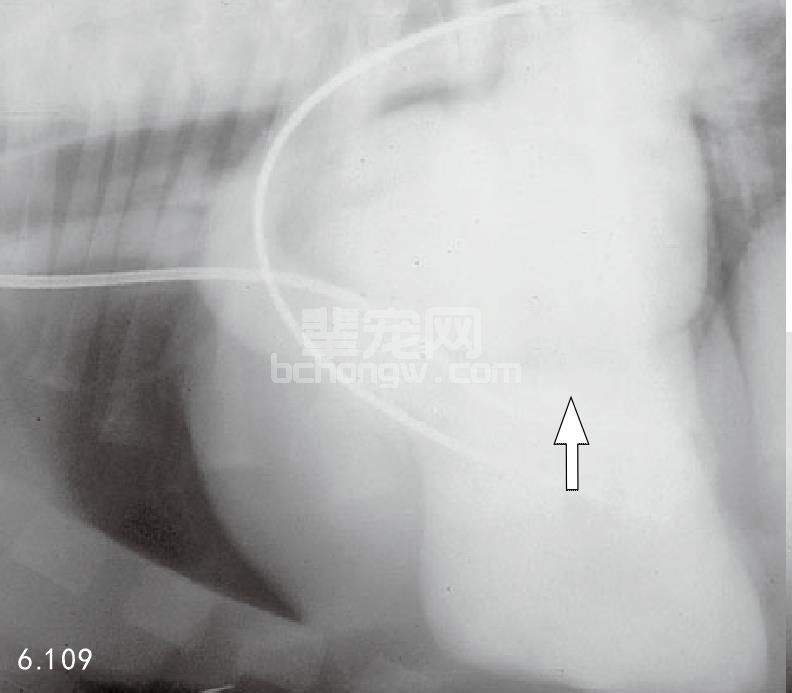

图6.109 左心室对比心血管造影,表明典型的二尖瓣回流和左心房肥大(箭头所指)(与6.107为同一患犬)。